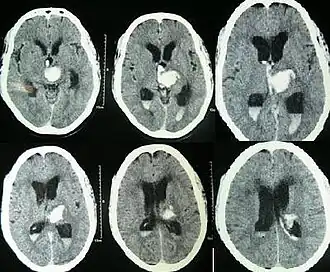

![]() | |

| CT scan of a spontaneous intracerebral bleed, leaking into the lateral ventricles | |

Intraparenchymal hemorrhage can be recognized on CT scans because blood appears brighter than other tissue and is separated from the inner table of the skull by brain tissue. The tissue surrounding a bleed is often less dense than the rest of the brain because of edema, and therefore shows up darker on the CT scan.[31] The oedema surrounding the haemorrhage would rapidly increase in size in the first 48 hours, and reached its maximum extent at day 14. The bigger the size of the haematoma, the larger its surrounding oedema.[32] Brain oedema formation is due to the breakdown of red blood cells, where haemoglobin and other contents of red blood cells are released. The release of these red blood cells contents causes toxic effect on the brain and causes brain oedema. Besides, the breaking down of blood-brain barrier also contributes to the odema formation.[13]